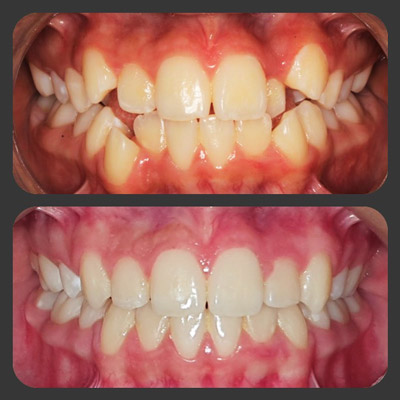

img

El paciente acudió a la consulta de ortodoncia por presentar una mala posición dental. Padecía de una función inadecuada para la masticación, y esto le imposibilitaba consumir adecuadamente los alimentos.